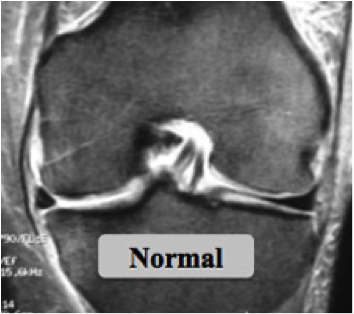

Des examens plus spécifiques comme l'IRM et l'arthroscanner sont demandés si les radiographies sont normales; ils vont permettre de visualiser les structures ménisco-ligamentaires et cartilagineuses de l'articulation.